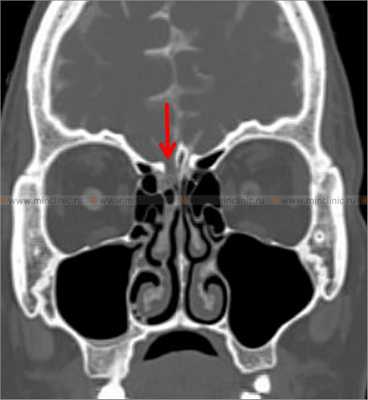

КТ-цистернография. Симптом «ликворной дорожки» — контрастированная СМЖ в правой половине полости носа (стрелка)

При компьютерной томографии костей черепа с цистернографией визуализируется костный дефект правой решетчатой пластинки (указано красной стрелкой).